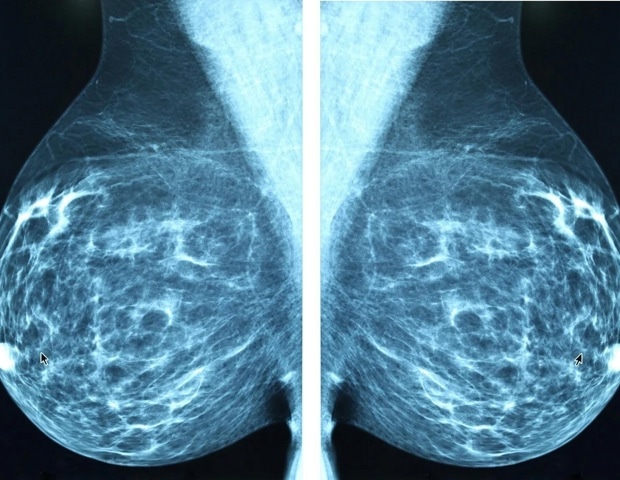

Sport: VALANX Biotech obtient 3 millions d’euros pour faire progresser l’ADC LIV-1 dans le cancer du sein métastatique triple négatif

Dernière contribution sur le web avec cette dénomination :VALANX Biotech obtient 3 millions d’euros pour faire progresser l’ADC LIV-1 dans le cancer du sein métastatique triple négatif Sur le web, un post curieux a éveillé notre intérêt VALANX Biotech (VALANX), une société de biotechnologie développant une technologie de conjugaison de protéines sélectionnable et spécifique à…